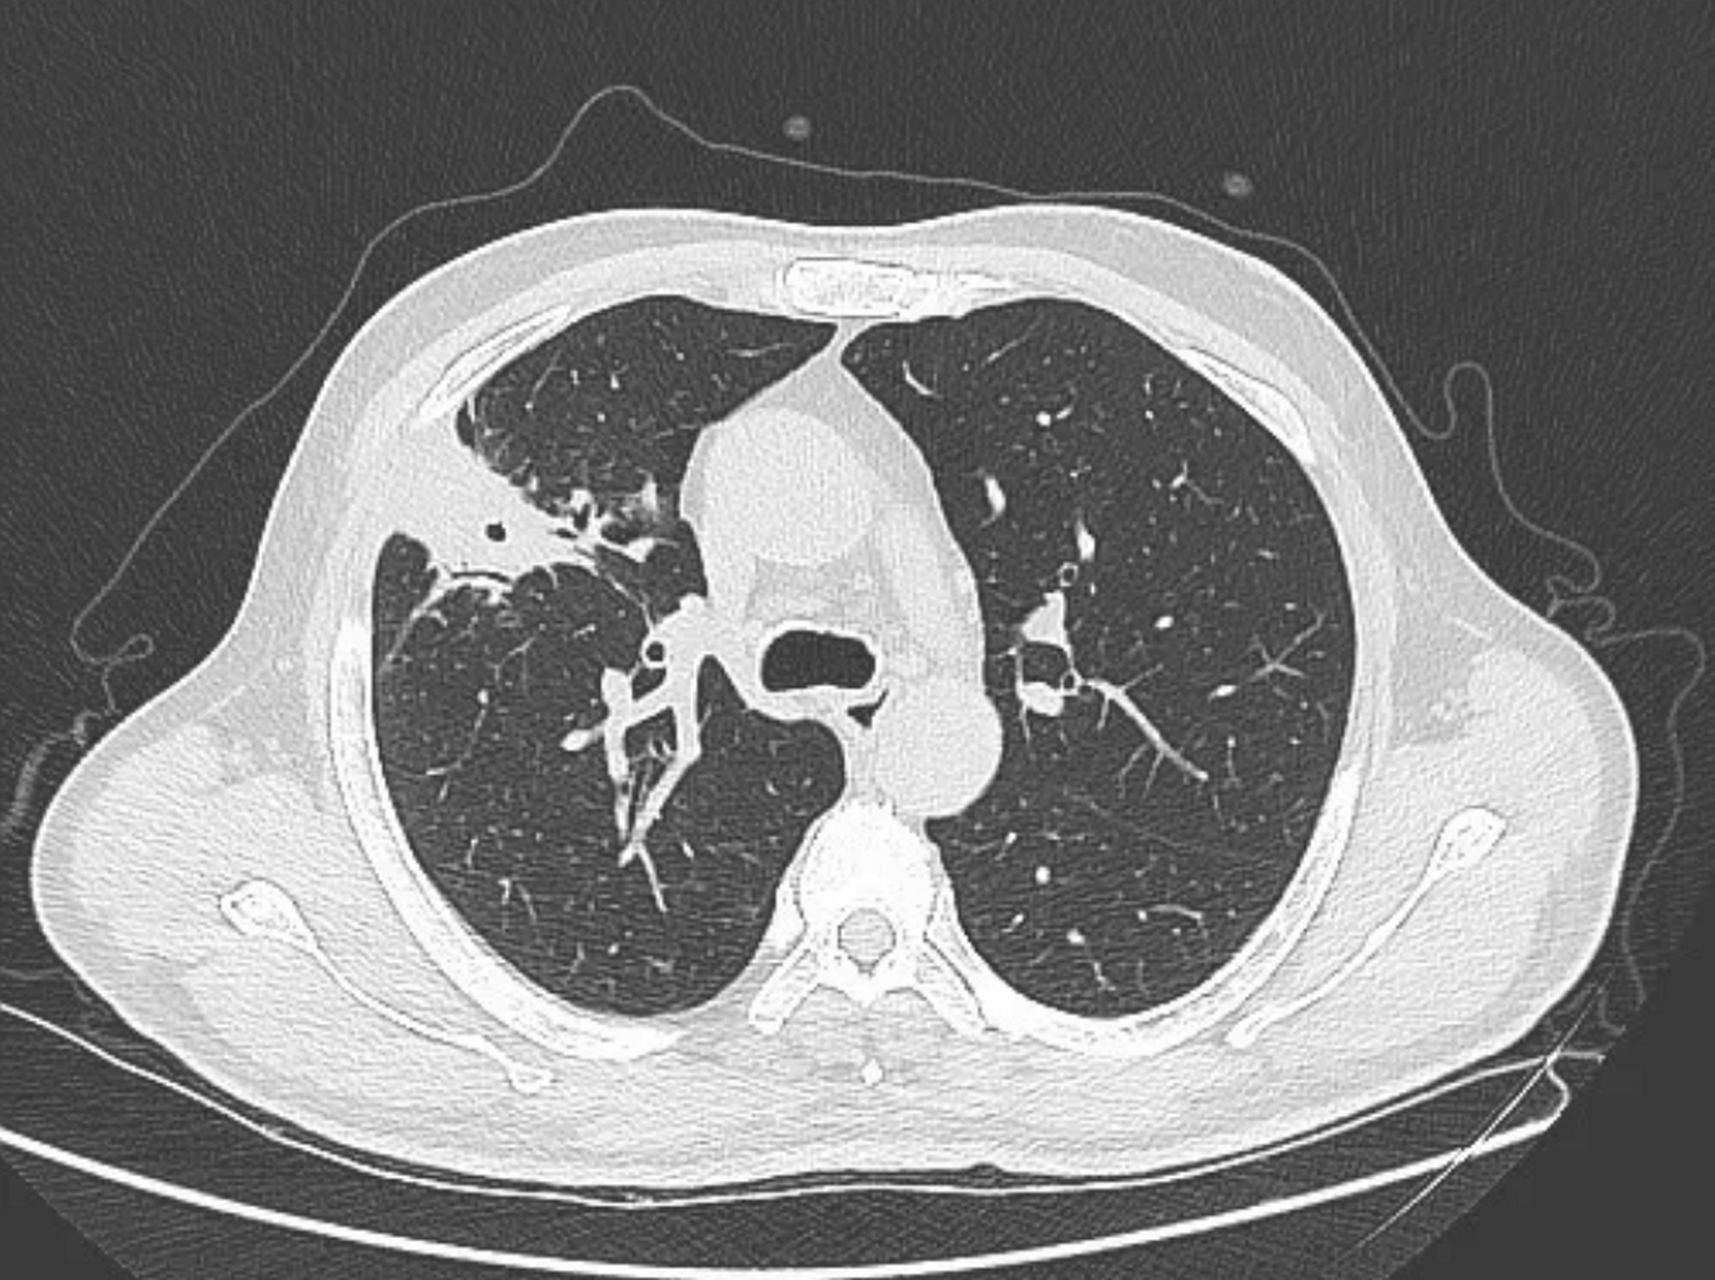

男性57岁,咳嗽,咳痰半月,肺脓肿猜病原体